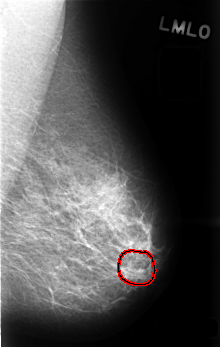

Digital Database for Screening Mammography

Volume: benign_13 Case: C-0487-1

C_0487_1.LEFT_MLO

LEFT_MLO LINES 4504 PIXELS_PER_LINE 2848 BITS_PER_PIXEL 12 RESOLUTION 50 OVERLAY

FILE: C_0487_1.LEFT_MLO.OVERLAY

TOTAL_ABNORMALITIES 1

ABNORMALITY 1

LESION_TYPE CALCIFICATION TYPE PLEOMORPHIC DISTRIBUTION CLUSTERED

ASSESSMENT 3

SUBTLETY 4

PATHOLOGY BENIGN

TOTAL_OUTLINES 1

BOUNDARY